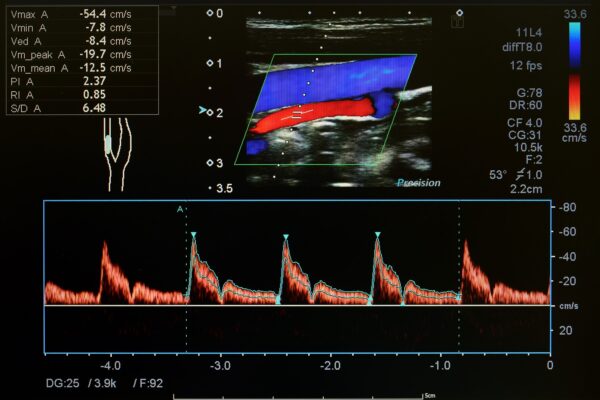

Duplex- und Dopplersonographie

Duplex- und Dopplersonographien sind spezielle Ultraschalluntersuchungen, mit denen Arterien und Venen, also Blutgefässe, beurteilt werden können. Der Schallkopf sendet Wellen in einer bestimmten Frequenz aus, die Wellen werden von den Blutkörperchen und den Gefässwänden in einer veränderten Frequenz reflektiert. Diese Veränderungen der Frequenzen hängen u.a. von der Bewegung der Blutkörperchen ab. Dadurch kann die Richtung des Blutflusses und die Fliessgeschwindigkeit des Blutes bestimmt werden. Dem Arzt ist es dadurch möglich, Einengungen (Stenosen) oder Verschlüsse von Blutgefässen zu erkennen. Die Methode ist völlig risikofrei und eignet sich zur Untersuchung sämtlicher Blutgefässe am Hals, an den Extremitäten (Arme und Beine) sowie im Bauchraum.

- Venenthrombosen an den Beinen (Venenverstopfung durch Blutgerinnsel)

- Arteriosklerose (Gefässverkalkungen durch Ablagerungen von Kalk und Fetten in den Arterien) zB bei den Halsgefässen zur Vorbeugung eines Hirninfarktes